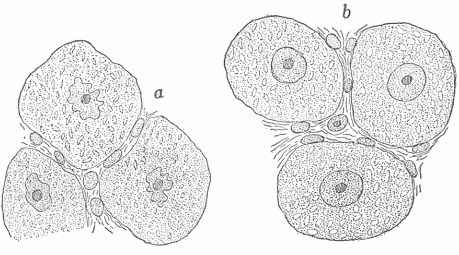

All the changes which take place in the cells are of great importance in conditions of both health and disease, for life consists in coördinated cell activity. The activities of the cells can be divided into those which are nutritive, those which are functional and those which are formative. In the functional activity the cell gives off energy, this loss being made good by the receipt of new energy in the form of nutritive material with which the cell renews itself. In certain cells an exact balance seems to be maintained, but in those cells whose activity is periodic function takes place at the expense of the cell substance, the loss being restored by nutrition during the period of repose. This is shown particularly well in the case of the nerve cells (Fig. 13). Both the functional and nutritive activity can be greatly stimulated, but they must balance; otherwise the condition is that of disease.

Fig. 13—Nerve Cells Of An English Sparrow (a) Cells after a day's full activity, (b) cells after a night's repose In (a) the cells and nuclei are shrunken and the smaller clear spaces in the cells are smaller and less evident than in (b). (Hodge)